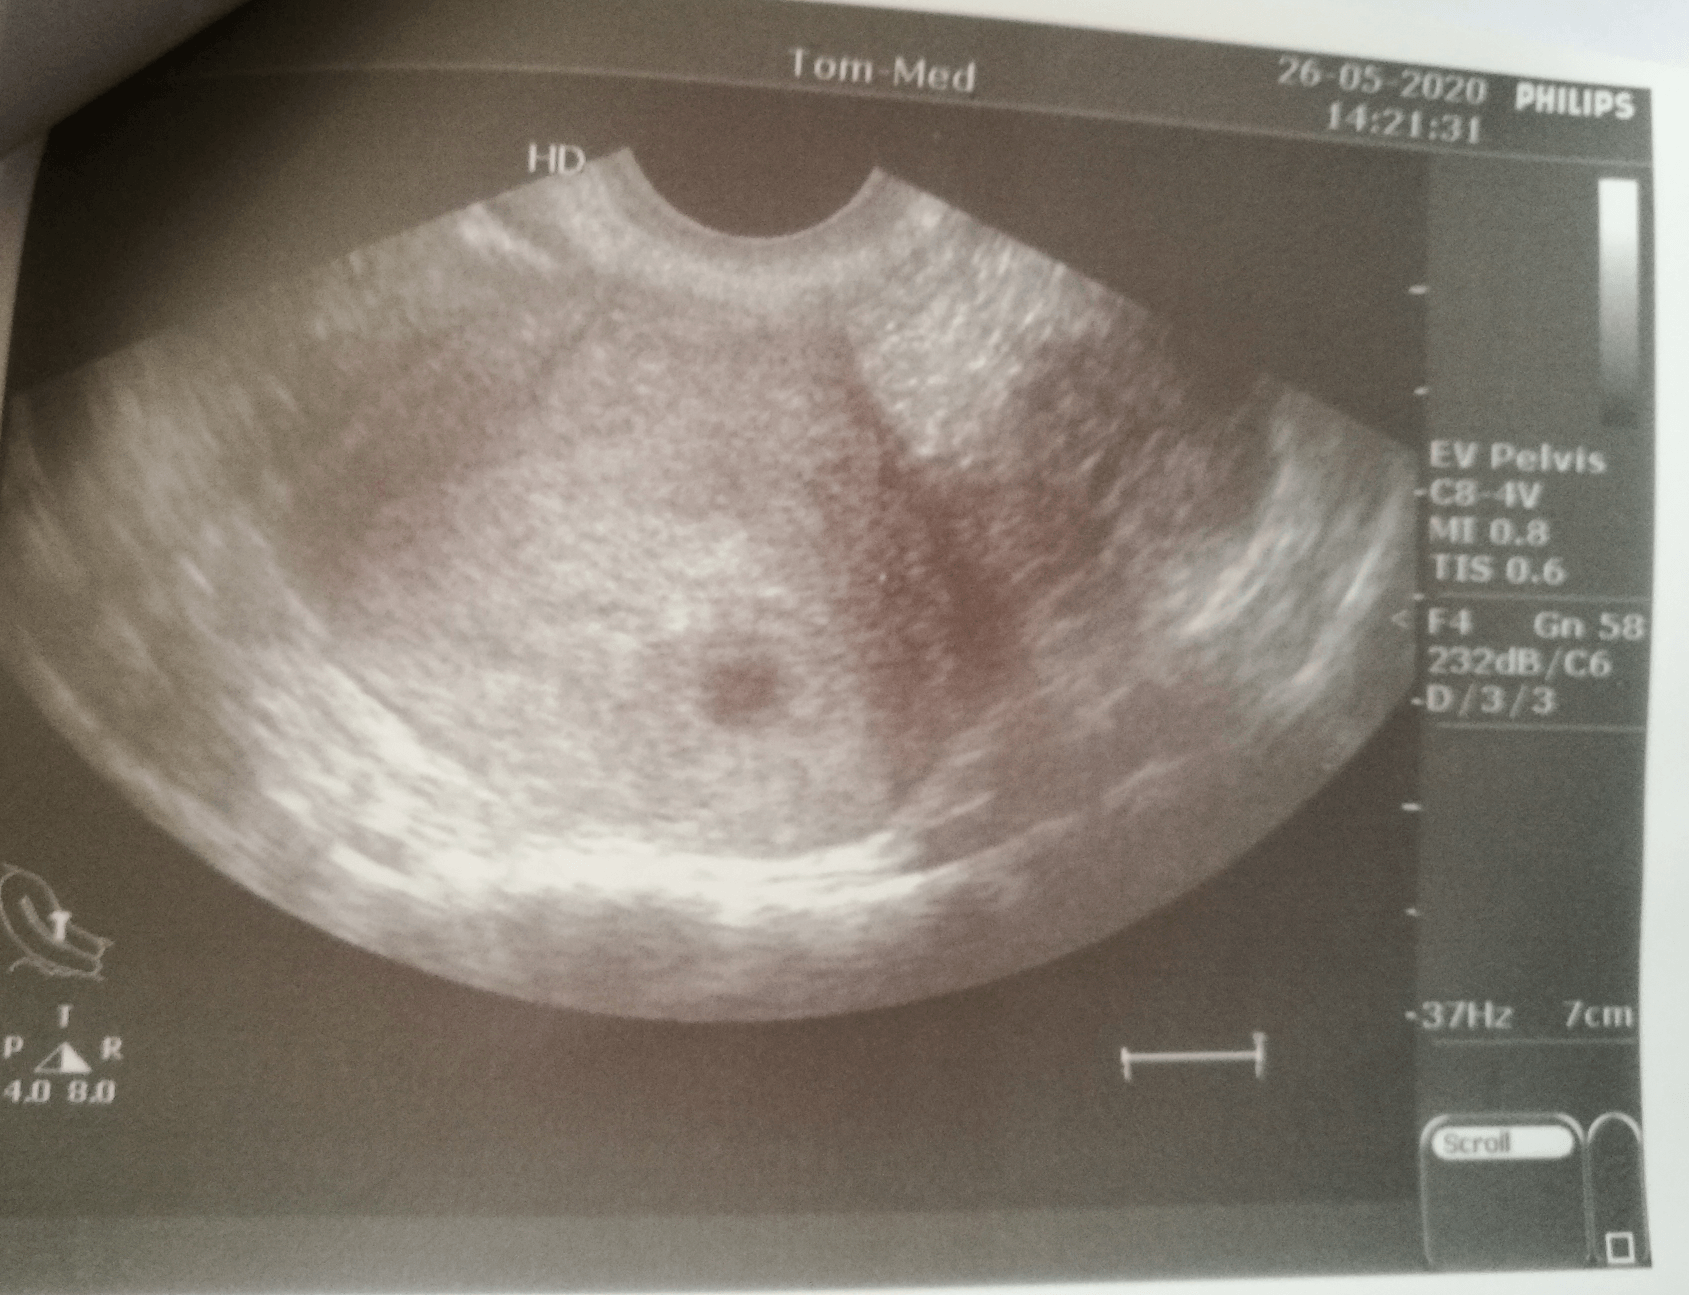

jestem po pierwszej wizycie

w zasadzie to nic nie wiem oprócz tego że ciąża jest i że ból piersi to dobry znak.... nawet lekarz nie liczył terminu powiedział tylko, że wg usg ciąża w 3cim tyg od zapłodnienia.

a tu wypociny 😂

Zobacz załącznik 1124875